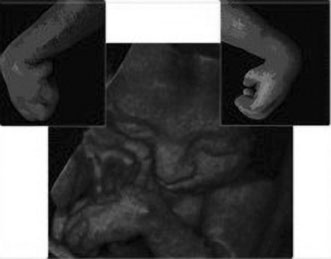

Maternal serum screening can identify pregnant women who are at an increased risk for having a baby with certain birth defects. Patient-specific risks for open spina bifida, Down syndrome and trisomy 18 (Edwards syndrome) (Fig. 1) can be determined by measuring the levels of certain proteins in maternal serum and combining those data with the patient's maternal age and clinical information.10 Women with a positive screen should be offered a definitive diagnostic test.

Fig. 1. Three-dimensional ultrasound showing typical pattern of trisomy 18. A clenched fist with the index finger overlapping the third and fourth fingers is distinctive of this disorder. Image courtesy of GE Medical Systems.